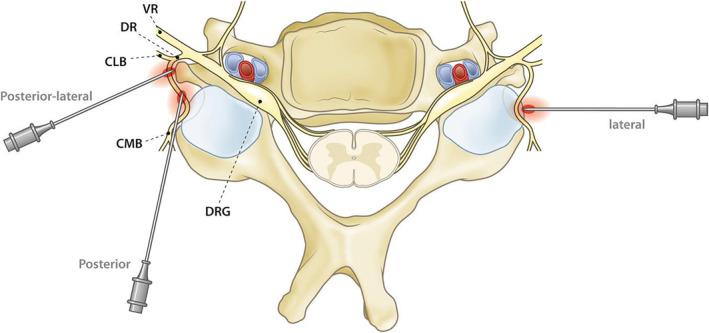

Facet-related pain is typically diagnosed based on history and physical examination of the patients, combined with a diagnostic block (eg, with local anesthetic) of the medial branches innervating the joints. There is no additive value for imaging techniques to diagnose cervical facet pain, but imaging may be used for procedure planning. First-line therapy for pain treatment includes focused exercise, graded activity, and range-of-motion training. Pharmacological treatment may be considered for acute facet joint pain; however, for chronic facet joint pain, evidence for pharmacological treatment is lacking. Considering the lack of evidence for treatment with botulinum toxin, intra-articular steroid injections, or surgery, these interventions are not recommended. Diagnostic blocks are not considered a viable treatment option, though some patients may experience a prolonged analgesic effect. Long-term analgesia (>6 months) has been observed for radiofrequency treatment of the medial branches.

小关节相关疼痛通常根据患者的病史和体格检查,结合对支配关节的内侧支进行诊断性阻滞(如使用局部麻醉剂)来诊断。成像技术对诊断颈椎小关节疼痛没有附加价值,但成像可用于手术规划。疼痛治疗的一线疗法包括针对性锻炼、分级活动和活动范围训练。急性小关节疼痛可考虑药物治疗;然而,对于慢性小关节疼痛,缺乏药物治疗的证据。考虑到肉毒杆菌毒素、关节内注射类固醇或手术治疗缺乏证据,不推荐这些干预措施。诊断性阻滞不被视为可行的治疗选择,尽管一些患者可能会有延长的镇痛效果。内侧支射频治疗已观察到长期镇痛(>6个月)。